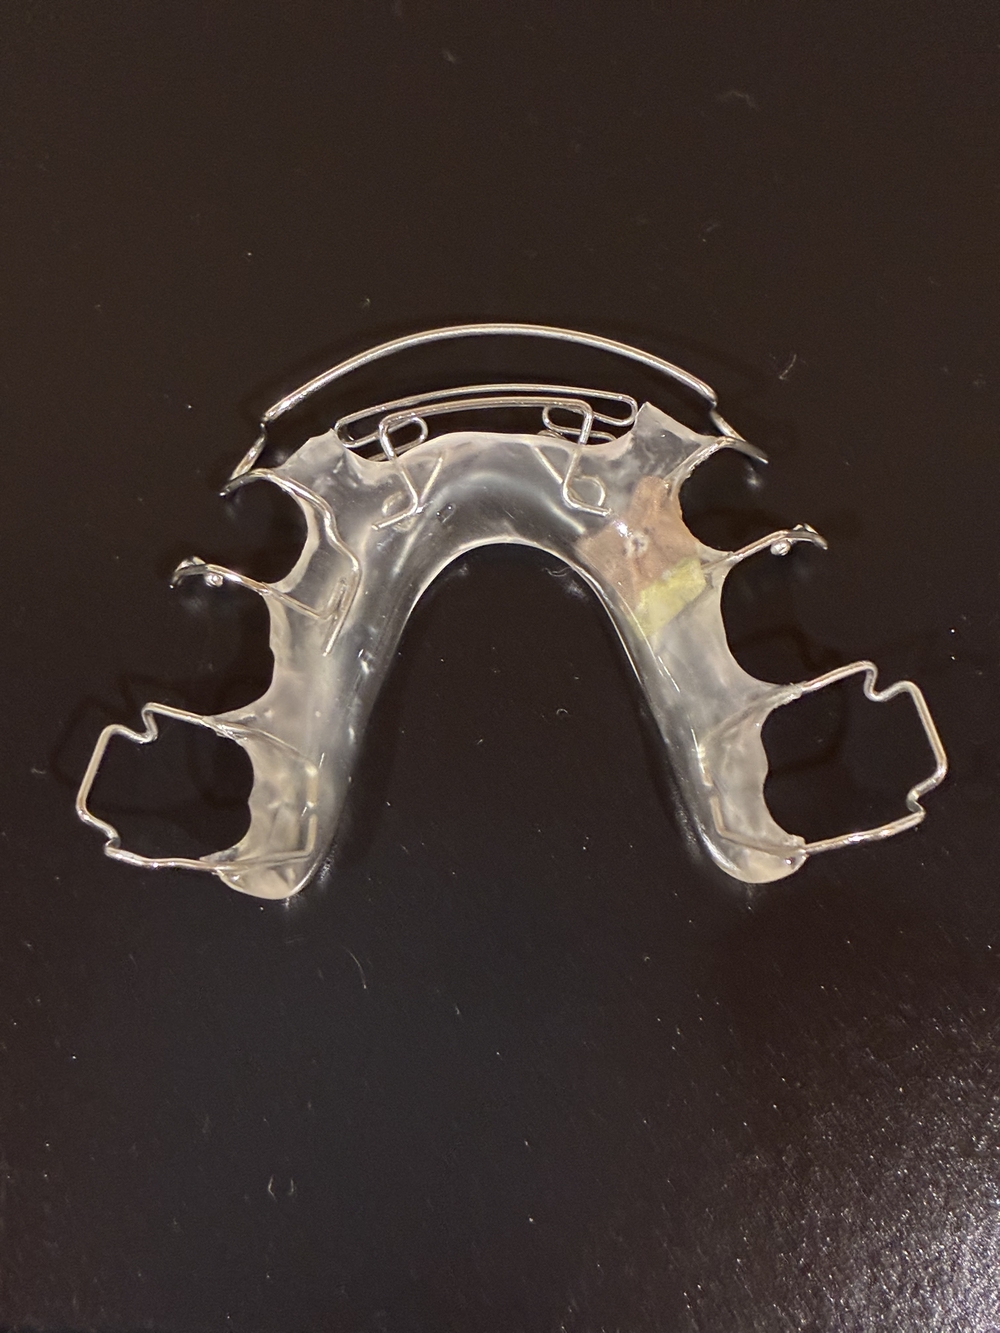

【下のリテーナー】